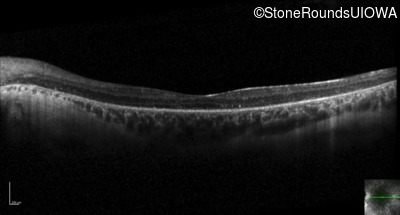

Optical Coherence Tomography - Right - 20/50 +1

Exemplar / OCT Stack

OCT Stack